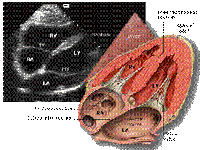

APICAL FOUR CHAMPER VIEW

Apical 4 chamber view

Structure from apex to base:

·Pericardium all around

·Apex at Top

·IVS ® central cardiac body ® IAS (Dividing the view into left 3/5 or 2/3 and Right 2/5 or 1/3).

·Left 3/5 or 2/3: LV(Lateral wall & cavity), MV(Leaflets & opening), ® LA(cavity & wall with openings of pulm. veins).

·Rt 2/5 or 1/3: RV(Lat wall & cavity), TV(Ant & Sept. leflets & opening) ® RA (cavity & wall).